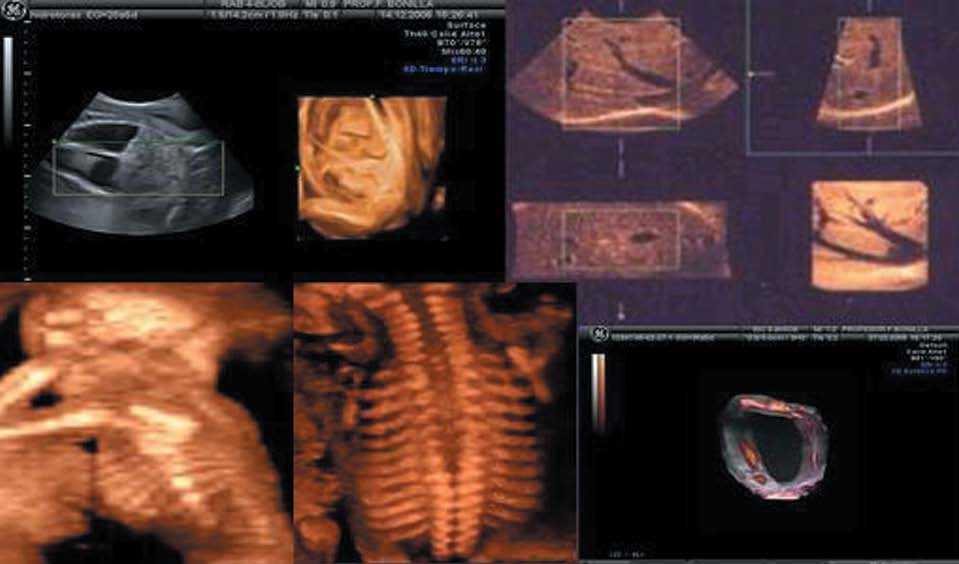

-- STIC: volumen 4D usando el software de correlación de imágenes espacio-temporales. Permite capturar el ciclo completo del latido del corazón del feto en tiempo real y guardar el volumen para el análisis posterior correlativo con el electrocardiograma (fig. 1A).

Figura 1.A) Reconstrucción 3D-4D de los arcos aórtico y ductal. STIC modo inverso. B) imagen B-Flow del arco aórtico. (Cedido gentilmente por General Electric.)

DeVore7, en el año 2003, describe el STIC. El volumen adquirido se estudió en un ciclo cardíaco repetitivo gracias al cine loop, y presentado en forma lenta para ver las diversas fases del ciclo cardíaco, las cámaras del corazón, las válvulas, el septo y el tracto del flujo de salida, sin aumentar la duración del examen. En modo superficie, permitió establecer diagnósticos de las alteraciones de la superficie y de las cámaras cardíacas11.

Al agregar al STIC, TIU, Doppler color, power o flujo B, se ha podido observar la representación hemodinámica, lo que facilita la demostración de los flujos durante un ciclo cardíaco en los diferentes planos seccionales escogidos11 (fig. 1A y B)

La representación del STIC con body glass mode, es ideal para demostrar la relación espacial o las diferencias de tamaño de los grandes vasos conectados con el defecto del septo ventricular, el cruce de los grandes vasos, la transposición de las grandes arterias o el origen de la arteria subclavia aberrante (fig. 6B).